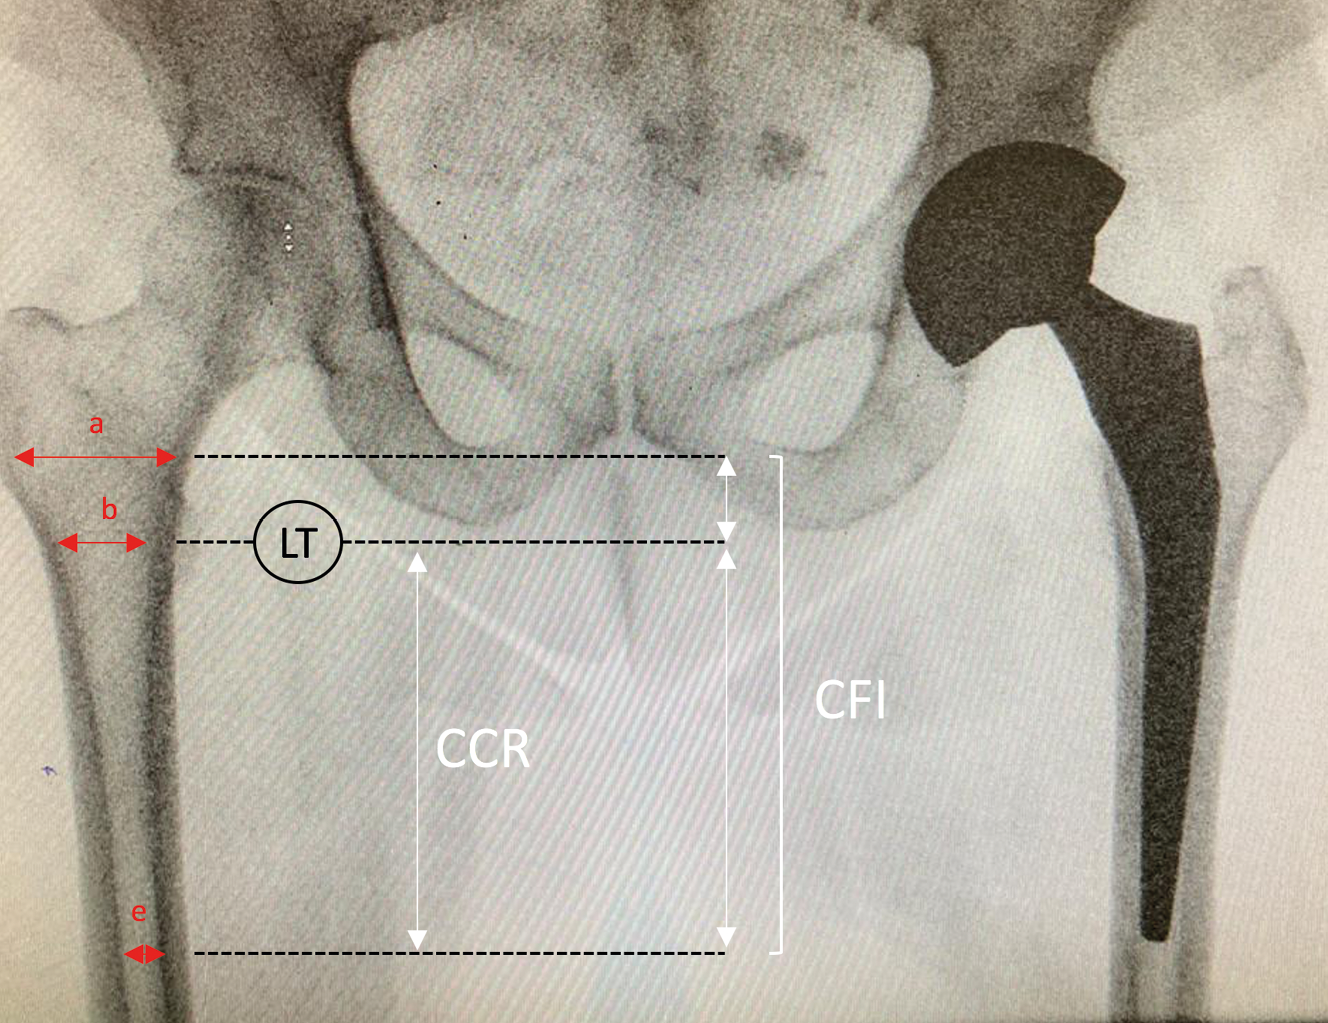

Femur shape was determined using the canal flare index (CFI) as measured on the preoperative x-rays.[15] Noble PC, Alexander JW, Lindahl LJ, Yew DT, Granberry WM, Tullos HS. The Anatomic Basis of Femoral Component Design. Clin Orthop Relat Res. 1988 CFI was defined as the width of the medullary canal 2cm above the lesser trochanter, divided by the width of the canal 10cm below the lesser trochanter. Using the criteria established by Noble et al., [15] Noble PC, Alexander JW, Lindahl LJ, Yew DT, Granberry WM, Tullos HS. The Anatomic Basis of Femoral Component Design. Clin Orthop Relat Res. 1988 a CFI < 3.0 was classed as a stovepipe canal shape, a CFI between 3.0 and 4.7 was classed as normal canal shape, and a CFI > 4.7 was classed as a champagne-fluted canal shape (Fig. 3). The canal calcar ratio (CCR) [16] Dorr LD. Total hip replacement using APR system. Tech Orthop. 1986 was also measured to establish femoral shape according the Dorr classification. [17] Issa K, Stroh AD, Mont MA, Bonutti PM. Effect of bone type on clinical and radiographic outcomes of a proximally-coated cementless stem in primary total hip arthroplasties. J Orthop Res Off Publ Orthop Res Soc. 2014 CCR was defined as the width of the medullary canal 10cm below the lesser trochanter, divided by the width of the canal at the lesser trochanter. A CCR < 50% was classified as Dorr type A, a CCR between 50 and 75% was classified as Dorr type B, and a CCR > 75% was classified as Dorr type C. Radiographic analysis was performed independently by two senior surgeons who knew neither the patient identity nor the surgical approach used.